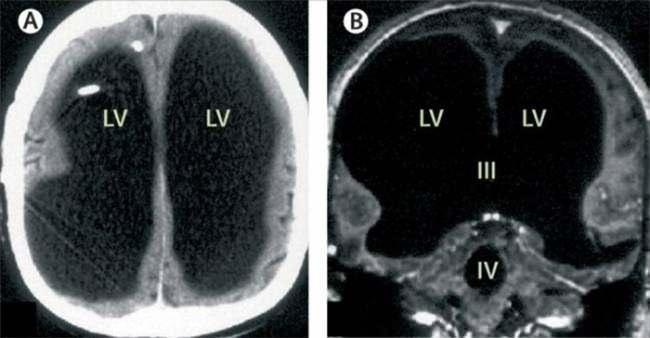

Hidrosefali, beyinde ve omurilikte üretilerek beyni dış tesirlerden müdafaaya yardımcı olan beyin omurilik sıvısının (BOS), beyindeki boşluklarda birikmesi ve baş içindeki basıncı artırması durumudur. Beyin omurilik sıvısı, bulunması gerekenden daha fazla olduğunda beyin dokularına ziyan verir, kafatasının fizikî yapısını bozar ve beyin işlevlerinde kalıcı bozulmalara neden olabilir.

Bebeklik devrinde kendisine “hidrosefali” teşhisi konulan adam, kafatasına stent takıldığını ve 14 yaşındayken geri çıkarıldığını belirtti. Doktorlar, adamın hastalığından ötürü beyninde sıvı biriktiğini ve bu nedenle 30 yılda beyninin yavaş yavaş tahrip olduğunu düşünüyorlar.